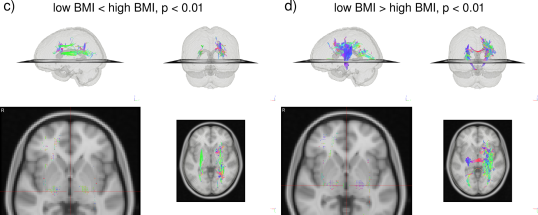

In the HCP dataset, ODFs correlate strongly with the demographic variable BMI. As expected, the ODFs negatively correlate (Fig. 7b) with BMI, indicating a loss of anisotropy with increasing BMI (Fig. 5a,b). This result is consistent with the well-established negative association between global white matter integrity and physical obesity (Mueller et al., 2011; Stanek et al., 2011; Verstynen et al., 2012; Gianaros et al., 2013; Verstynen et al., 2013). The fiber directions (Fig. 8a,b) identified from can be used to perform tractography (Fig. 8c,d). Resulting tracts (Fig. 8c,d) show a pronounced loss of anisotropy in the corticospinal tracts, the optic radiations and the right superior longitudinal fasciculus. These results are corroborated by the existing methods TBSS (Fig. 9a,b, S2a,b), Connectivity-based fixel enhancement (Fig. 9c,d, S2c,d) and local connectometry (Fig. 9e,f, S3a,b). The volume of positive findings of correlation with BMI is largest when using the full ODF information with the ODF approach (Fig. 9). In addition, in a test of specificity, no voxels are found to correlate with randomly permuted BMI (Fig. S4).

The HCP ODFs also correlate with neurocognitive measures (Fig. 10 and 11). Walking endurance (Fig. 10a and 11a) predictably relates to the corticospinal tract, while the frontal part of the corpus callosum indicated in gait speed has been identified before when comparing endurance athletes with non-athletes (Raichlen et al., 2016) and when studying the effect of treadmill training after stroke (Enzinger et al., 2009). Language recognition and comprehension tasks (Fig. 10b and 11b), as measured by the Oral Reading and Picture Vocabulary test, correlate with ODFs in areas identified by fMRI work (Berl et al., 2010): posterior superior temporal gyrus and inferior frontal gyrus connected by stretches of the arcuate fasciculus pathway/superior longitudinal fasciculus III. Besides these areas, language comprehension also relates with ODFs in the medial frontal gyri and the left precuneus (Schmithorst et al., 2007). Our analysis further connects the Episodic Memory measure with the posterior cingulate and precuneus, though not with the medial temporal cortex (Fig. 10c and 11c). These areas have been shown to deactivate in episodic memory tasks (Dickerson and Eichenbaum, 2010). Lastly, Fluid Intelligence correlates widely with ODFs in the prefrontal, parietal and temporal cortex as indicated before (Gray et al., 2003) as well as with ODFs along tracts connecting these regions (Fig. 10d and 11d).